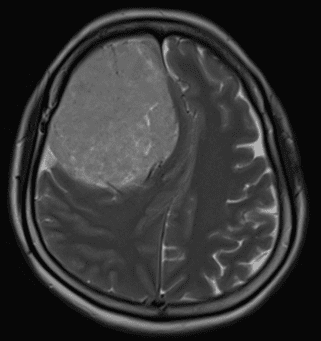

Bệnh nhân nhập viện với triệu chứng đau đầu dữ dội, nôn ói và yếu nửa người trái kéo dài khoảng 6 tháng. Hình ảnh MRI cho thấy khối u chèn ép nhiều lên các cấu trúc não của bán cầu phải. Sau khi được hội chẩn chuyên khoa và chuẩn bị kỹ lưỡng, ekip phẫu thuật đã tiến hành mở sọ lấy trọn khối u và gửi mẫu giải phẫu bệnh.

Hình ảnh MRI trước mổ (trái), CT sau mổ (giữa), khối u (phải)